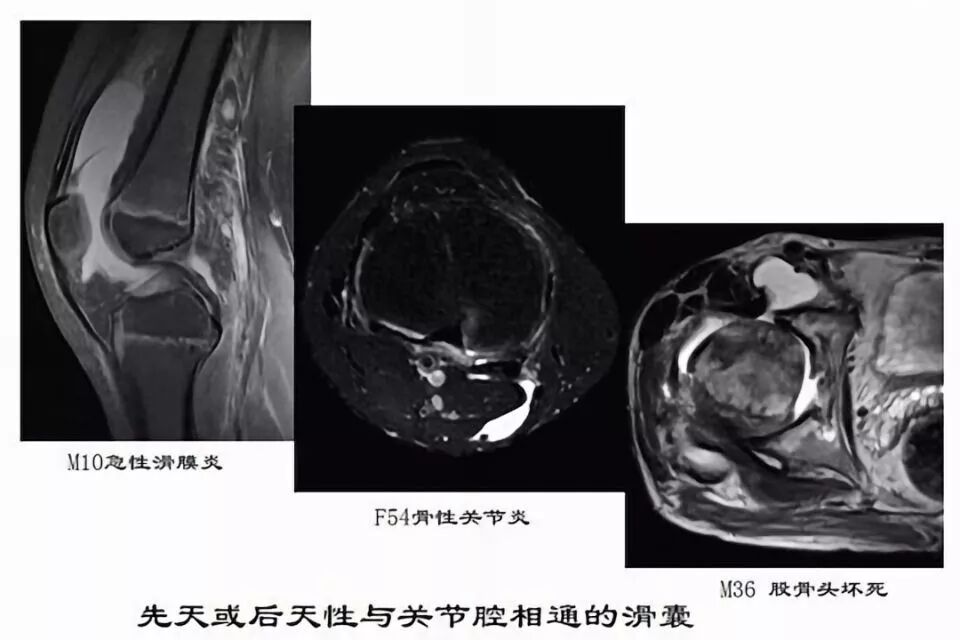

滑囊是关节囊外的囊性结构,可与关节囊相通,其作用是减少肌腱、骨和皮肤之间的摩擦。可以分为先天性滑囊和获得性滑囊。